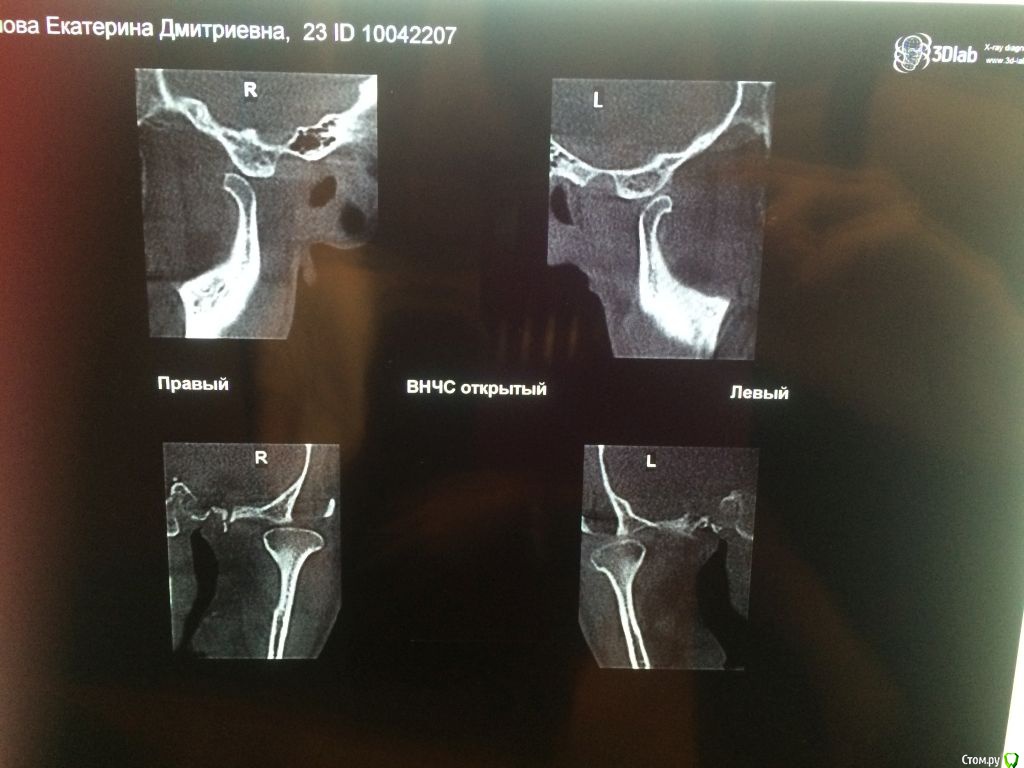

Добрый день! Очень прошу помочь с выбором врача или рекомендаций по лечению. С 2010 по 2012 год я носила брекеты (зубы были ровные, но с левой стороны верхня челюсть полностью перекрывала нижние, не было контактов, происходило стачивание). Затем с 2012 по 2016 год мне пытались исправить зубы нижней челюсти, я носила разные каппы, пластинки, то есть зубы все это время не фиксировали в определенном положении. Затем наконец в 2016-2017 году я относила полгода корректирующую каппу, которая более-менее выровняла мне нижний ряд (там была скученность). Все это время пломбы на жевательных зубах мне не меняли, они очень сильно сточились, и мне рекомендовали их заменить. Но как раз в это время у меня заболел сустав с правой стороны (на фото он соответственно слева, где и наблюдается ассиметрия). Я стала ходить по ортодонтам-ортопедам, одни говорили, что у меня все супер с прикусом, другие говорили, что клыки не под тем углом и надо снова ставить брекеты. Устав от хождений, я обратилась за диагностикой в небезызвестный центр междисдисплинарной стоматологии. Сделала там полную диагностику, по результатам которой мне предложили либо исправить брекетами клыки и поднять прикус керамическими вкладками, либо без брекетов, но тогда ставить на клыки также вкладки. Эта процедура проводится аж в три этапа и стоит как крыло самолета. Я прилагаю результаты моей диагностики. Обратилась за консультацией к другому ортопеду, который заверил, что можно обойтись временными и затем керамическими вкладками. Но помимо прикуса меня волнует ассиметрия улыбки, которая появилась в последнее время. Во-первых, я вижу невооруженным глазом, что зубы с правой стороны по высоте короче, чем с левой, то есть они меньше закрывают нижние зубы, чем с противоположной стороны, это же видно и на фото. Во-вторых, справа уголок губы при улыбке опускается как бы к низу, в отличе от левой стороны, где он идет ровно. В-третьих, с этой же правой стороны при улыбке мыщца начинается дергаться... Сейчас я уже запуталась, к какому врачу мне обращаться с данной проблемой: к ортодонту, к ортопеду, либо это гипертонус мыщц (хотя в закрытом состоянии эта ассиметрия не так заметна) Заранее благодарю за рекомендации.

Вам необходим врач-ортокраниодонт. Пытаться найти решение проблемы только на уровне зубов будет крайне трудно, да и бесполезно. Это сравнимо с симптоматическим лечением, когда идёт борьба только с симптомами заболевания, но никак не влияя на главную причину. Природа Ваших проблем (ДВНЧС, асимметрия) кроется в черепе, а точнее, в имеющимся его искажении